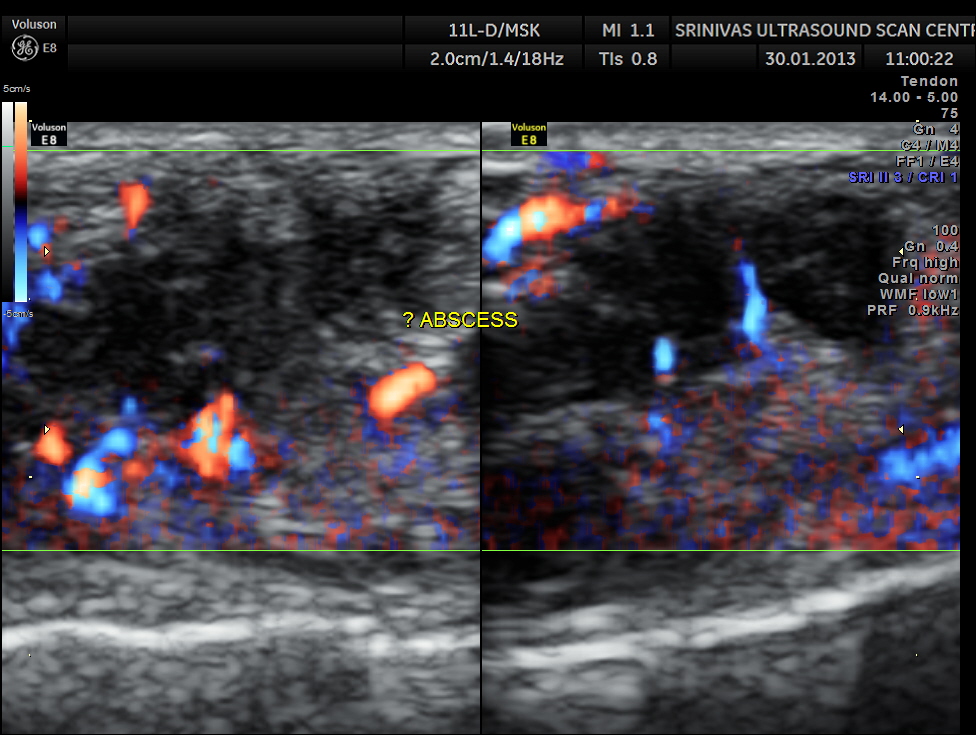

An indistinct hypo echoic mass was seen under a tendon and was well away from the surface of the bone .

Colour Doppler showed increased vascularity all around .

A diagnosis of an abscess in formation was offered and the child recovered well with appropriate treatment.